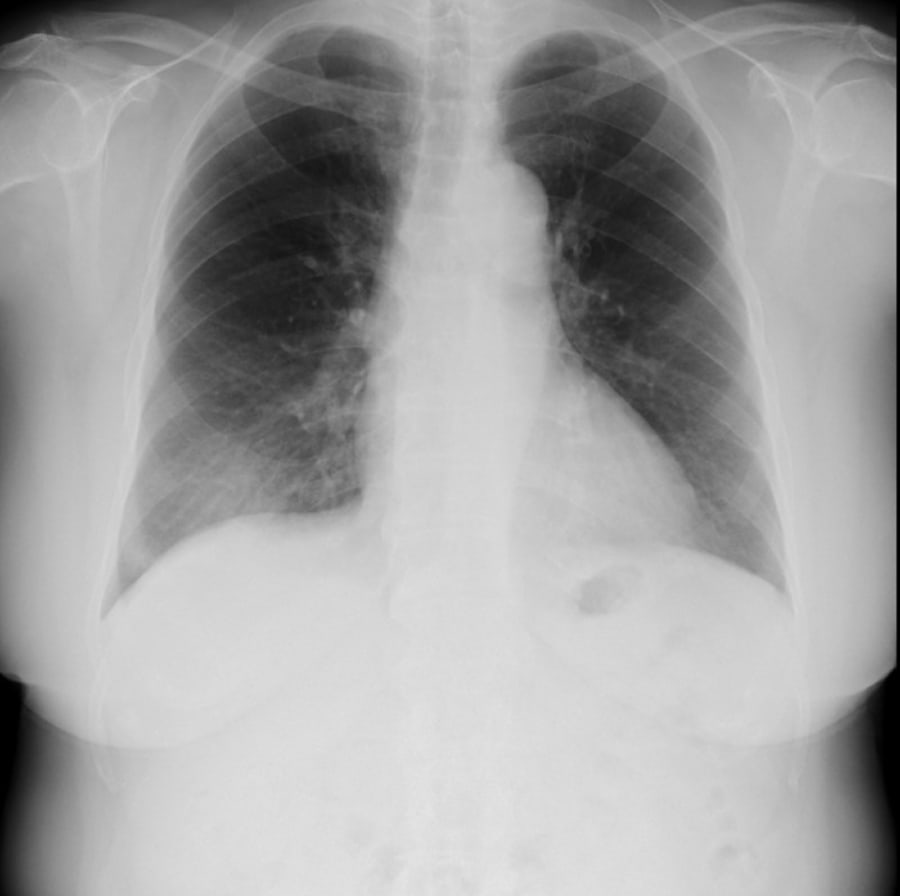

EIRL Cloud 利用イメージ

四角いボックスはEIRL Chest XR *1が検出した肺結節候補域❷と浸潤影候補領域❶を表示しています。

※EIRL Viewer *2による表示例です

*1 製造販売承認番号:30400BZX00285000 販売名:医用画像解析ソフトウェア EIRL Chest XR

*2 販売名:医用画像ビューワソフトウェア EIRL Viewer 製造販売認証番号:303AGBZX00046000